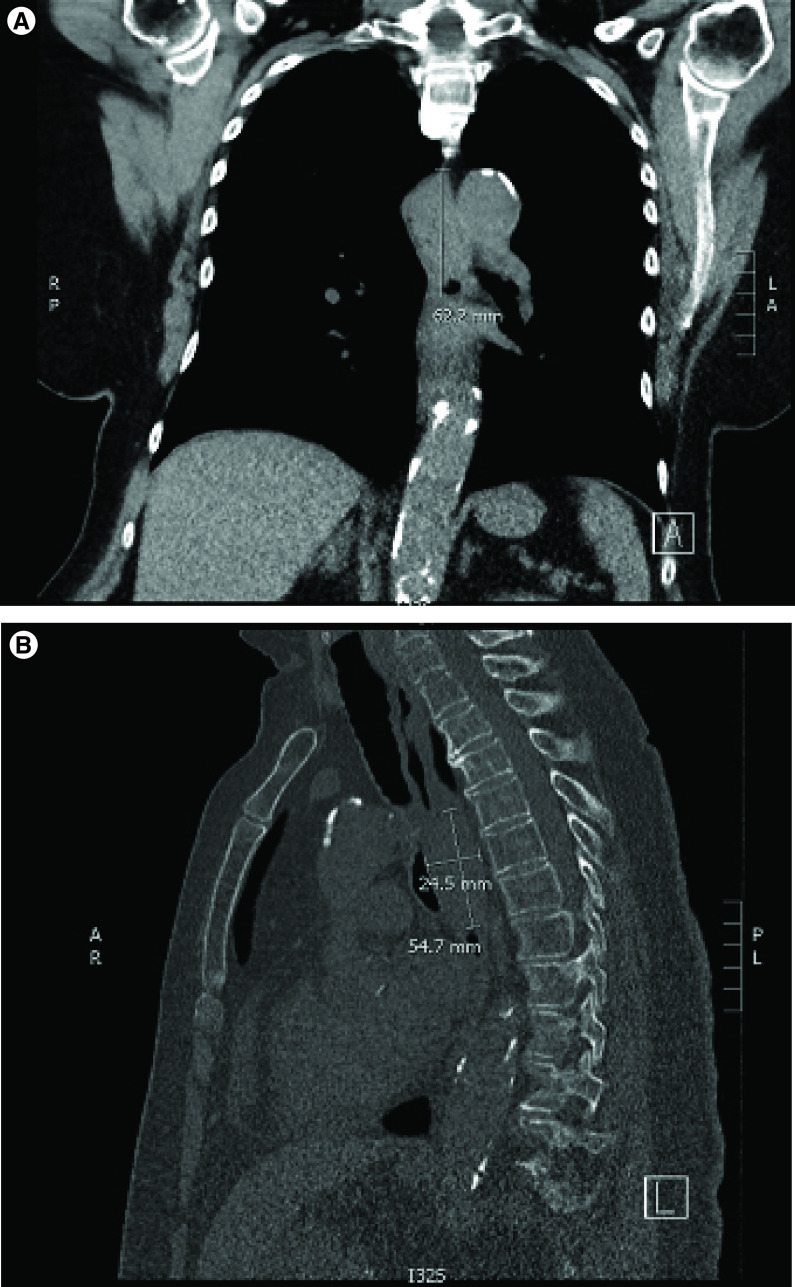

On initial investigation, a chest x-ray revealed a curvilinear density near the distal trachea and proximal right main stem bronchus. Subsequent low-dose computed topography (CT) imaging was obtained which noted a soft tissue mass, likely intraluminal, measuring 3.1 × 2.6 × 5.5 cm (Figure 1). The patient underwent an upper esophagogastroduodenoscopy (EGD) and bronchoscopy. The bronchoscopy revealed extrinsic compression, but no airway involvement. The EGD confirmed the presence of a large tumor spanning the proximal esophagus from 21 to 29 cm from the incisors (Figure 2).

Figure 1. . Computed tomography images of esophageal mass.

( A) Coronal images of thorax. ( B) Sagittal images of thorax. Arrows indicate esophageal mass. Measure bars recorded in ml.